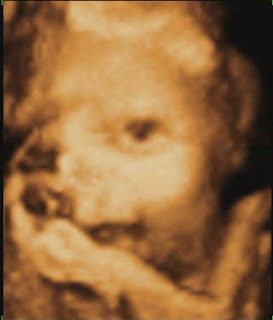

Dumnezeule….ce sentiment mi-a dat ecografia 3D….:X.Sa fie sanatos/sanatoasa…..App, de ce nu ai pus photo cu sexul…>:P Reply